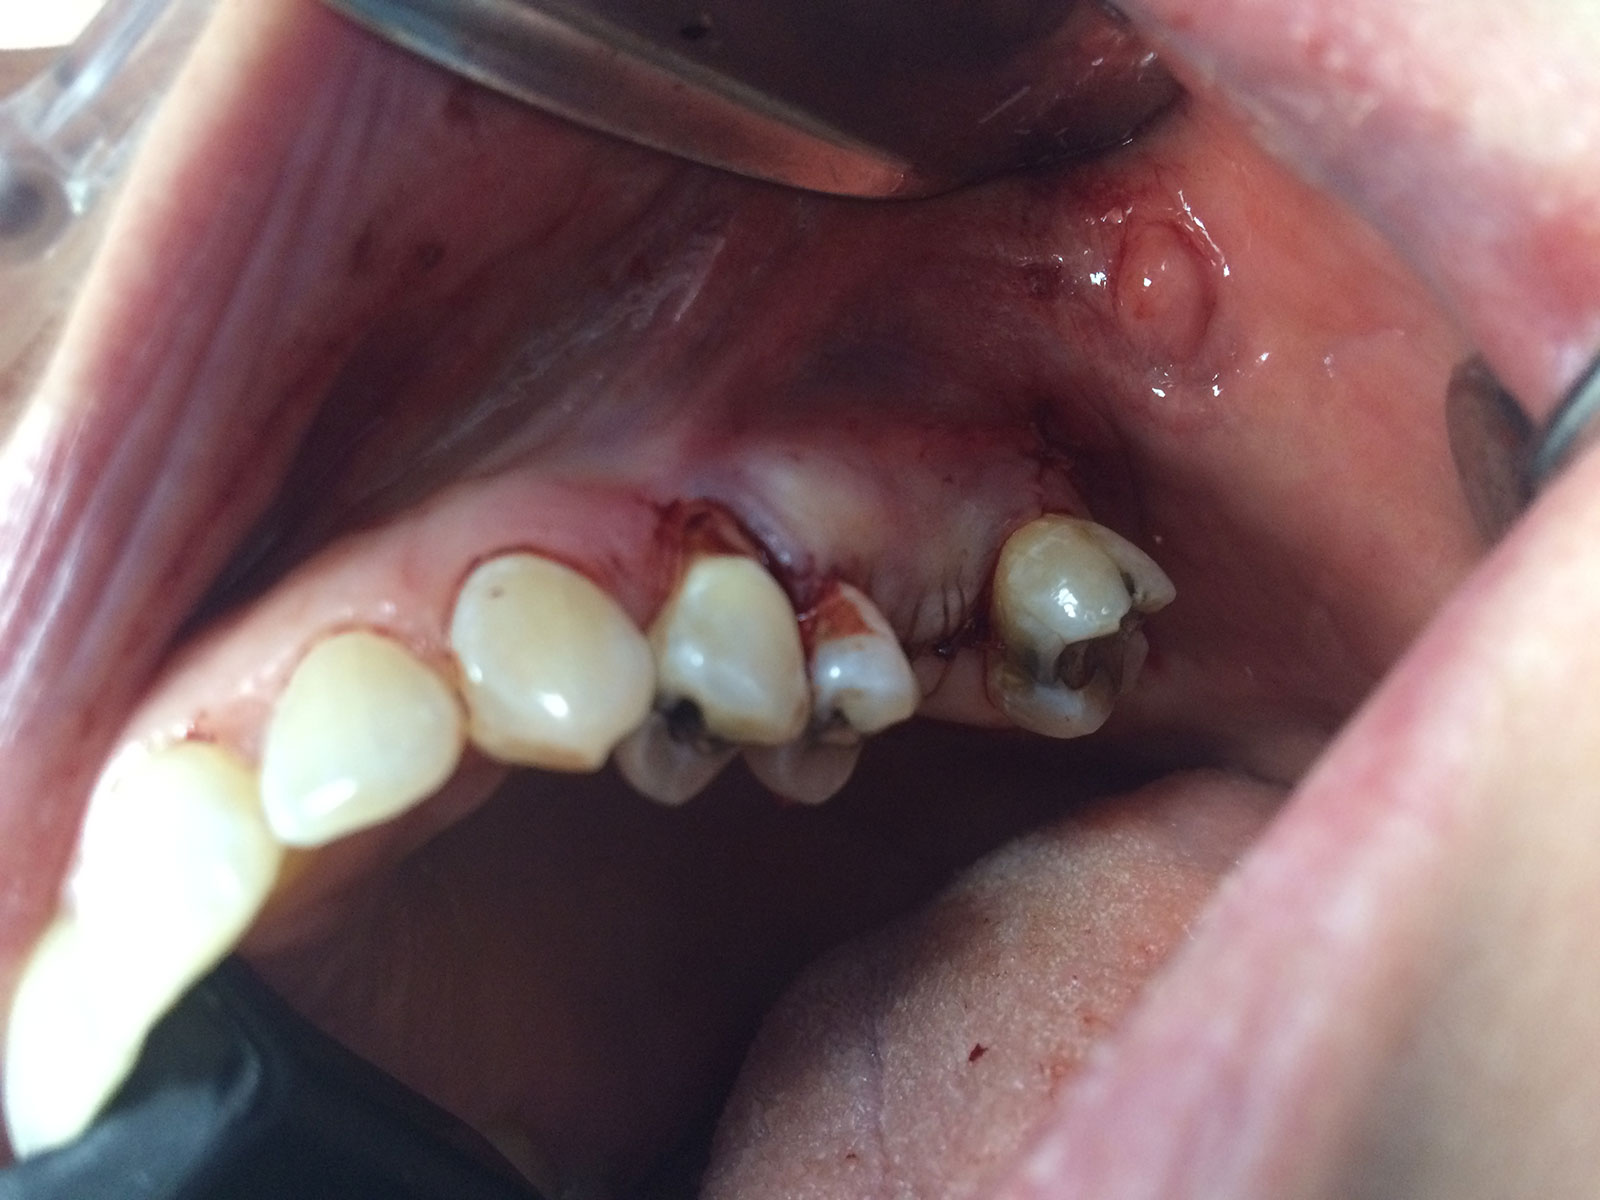

Sinus Grafting Procedures

A sinus grafting procedure, also known as a sinus augmentation, is for patients who have insufficient natural bone in the areas where dental implants are needed. They are long lasting, strong and sturdy, and fit and function like natural teeth. The procedure involves adding bone, either your own natural bone from another part of the body, from a donor or made of processed or synthetic bone material, and placing it below the sinus so that the implants can be placed. After the bone has healed and developed, usually around four to 12 months, the dental implants can be placed.

The photos on this website are from real surgeries performed by Dr. Ulloa. Due to the

graphic nature of the images and content, viewer discretion is advised.